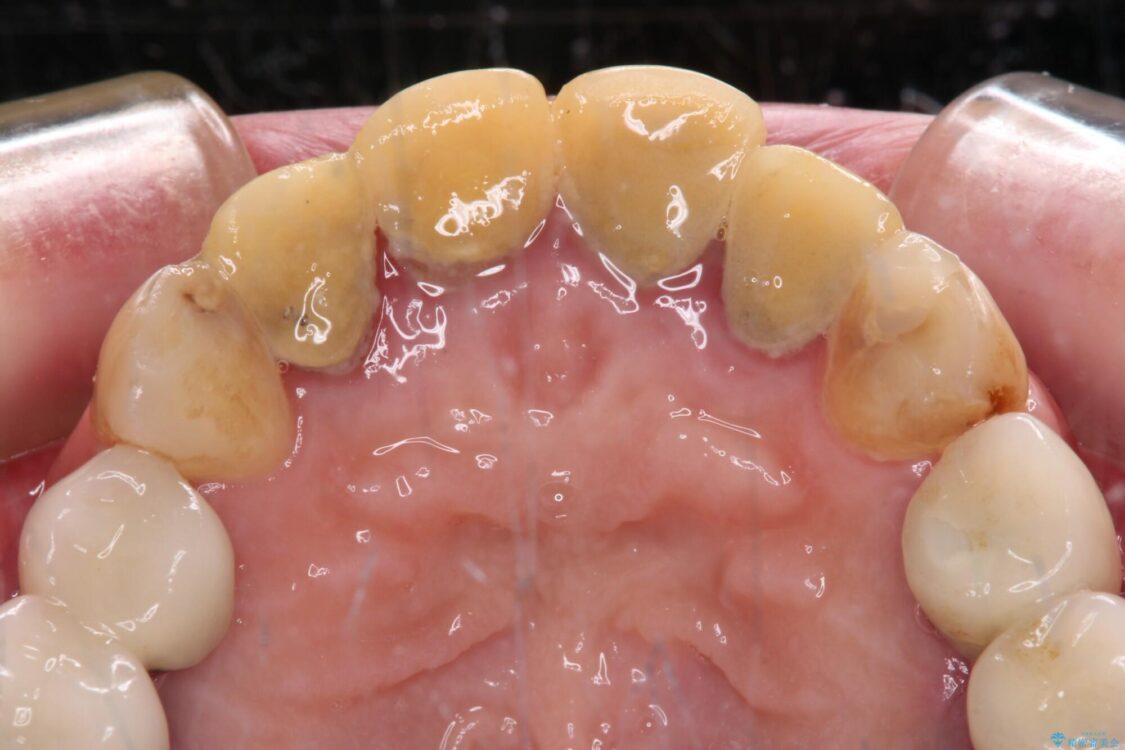

仮歯装着後に放置してしまい、恥ずかしいとのことで来院された患者様です。

仮歯が不適合で歯肉が腫脹していたため、しっかりと調整した新しい仮歯にして腫れを改善した上で、オールセラミッククラウンにて補綴することとしました。

治療前

• 仮歯のまま放置した前歯 オールセラミッククラウンで自然な前歯に 治療前画像